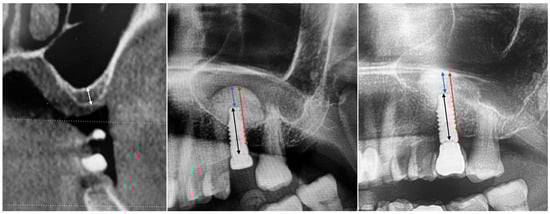

The present retrospective study evaluated data collected from any partially edentulous patient, aged 18 years or older, rehabilitated in the posterior maxilla (premolars and molars) with at least one tissue level implant in combination with sinus lift by a crestal approach, with a minimum residual bone height (RBH) of 2 mm, between September 2021 and October 2024. Data from 36 potential candidates were initially included. Of these, only 15 patients with 20 implants met the inclusion/exclusion criteria. Of the 21 excluded patients, 16 did not have the panoramic radiography at the crown delivery. Three patients did not receive the final crown due these patients moved in an other city. Two patients had serious health problems (one had an heart attack and one a stroke). All the included patients had a radiographic control nine months after implant placement. The mean follow-up was 19.5 ± 6.4 months (from 9 to 30). None of the implants or prostheses failed, and no technical or biological complications were experienced. The mean residual bone height (RBH) at implant placement was 4.2 ± 1.4 mm (from 2.0 to 6.7 mm). The overall membrane elevation was 13.8 ± 1.8 mm (from 10.9 to 17.8). The difference baseline (RBH) was 9.6 ± 2.4 mm (from 5.7 to 14.3; p = 0.000). The amount of bone above the implant tip was 3.4 ± 1.7 mm (from 1.3 to 7.9). At the nine-month follow-up, the overall membrane elevation was 13.0 ± 1.6 mm (from 10.4 to 16.1). The difference comparing with implant placement was 0.8 ± 0.7 mm (from 0.0 to 2.6; p = 0.000). The amount of bone above the implant tip was 3.0 ± 1.2 mm (from 1.3 to 5.7 mm). The difference comparing with implant placement was 0.4 ± 0.6 mm (from 0.0 to 2.3; p = 0.007). Data and an explanatory case are reported in Figure 1 and Table 2(a), (b).

Figure 1.

From left to right: preclinical situation, implant placement and sinus lift, nine months after implant placement. White line: residual bone height (RBH); black line: implant length; red line: overall amount of bone (OAB); blue line: bone above the implant tip (BAI).